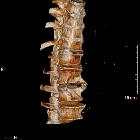

scalloping Wirbelkörper

Deformierte

Wirbelkörper thorakolumbaler Übergang bei Achondroplasie. Die Vorderkante ist ausgerundet, die Hinterkante zeigt ein Scalopping.